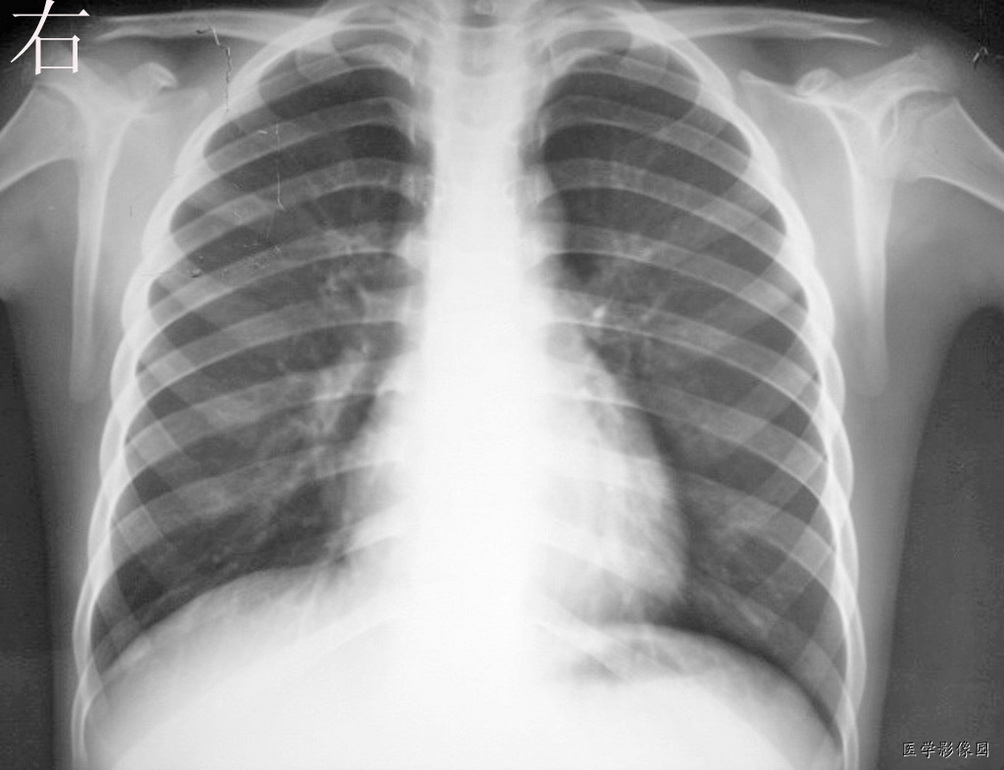

男,9岁.咳嗽发烧3天,t37---39.  请各位发表意见

双肺纹理增粗紊乱,以右下肺为著。考虑支气管炎。建议抗炎后复查

双肺纹理增强,右肺门影增浓,支持考虑支气管炎。

如果这个片子肺纹理增强,那么基本的片子没有不报增强的。